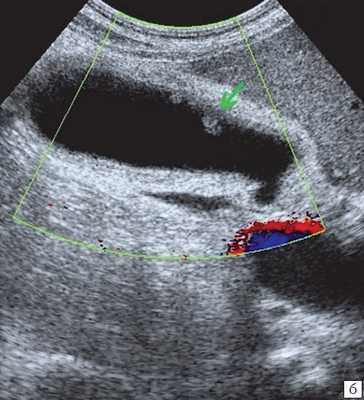

(Слева) На поперечной трансабдоминальной сонограмме в ямке желчного пузыря визуализируется эхогенная структура изогнутой формы с акустической тенью — изменения, характерные для «фарфорового» желчного пузыря.

(Левый) Пример полного кальциноза: у пациентки 67 лет, жалующейся на периодические боли в области желчного пузыря, при сканировании в черно-белом режиме в ямке желчного пузыря определяется тонкая гиперэхогенная полулунная линия, отбрасывающая плотную акустическую тень.

(Правый) У этой же пациентки в той же области в правом верхнем квадранте ожидаемо определяется диффузная криволинейная линия кальциноза, повторяющая контуры желчного пузыря.